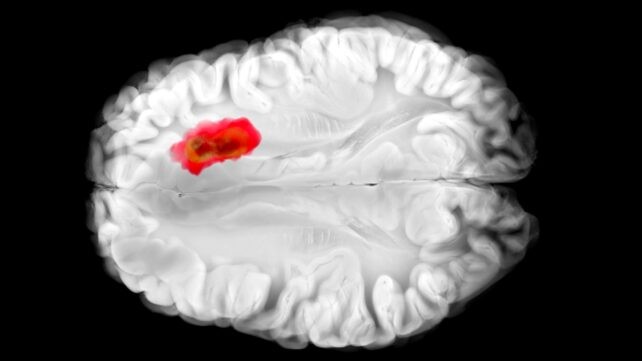

Hydralazina é um medicamento antigo que tem sido usado para tratar a hipertensão há décadas, mas seu funcionamento exato nunca ficou completamente claro. Um estudo recente, liderado por uma equipe da University of Pennsylvania, revelou que a droga bloqueia uma enzima chamada 2-aminoethanethiol dioxygenase (ADO). Essa enzima, por sua vez, acredita-se que desempenha um papel em glioblastoma agressivo. Essa nova compreensão da hidrala zina pode abrir o caminho para novos tratamentos contra o câncer, bem como melhorar a eficácia do medicamento para seus alvos atuais.

ADO é descrita como um “alarme” que alerta o corpo para a queda de oxigênio. Ela dispara uma cascata que aperta os vasos sanguíneos ao destruir as proteínas RGS (reguladores da sinalização da proteína G). Tumores de glioblastoma costumam apresentar altos níveis de ADO, sequestrando-a para produzir um químico chamado hipotaurina, que ajuda as células cancerígenas a se espalharem, sobreviverem por mais tempo e tolerarem o estresse. Até este estudo não havia inibidores conhecidos de ADO. Em experimentos com células humanas de glioblastoma, a hidralazina interrompeu o crescimento tumoral bloqueando ADO.